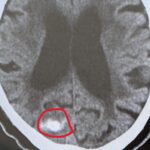

救急科

1週間前から、元気がない、話がおかしい ということで ご家族がつれて、受診されました。 血圧が200以上あり、MRIで脳梗塞を認めました。 また首の血管がさけており(椎骨動脈解離) 総合病院に救急搬送しました。 これから一人暮らしが増える時代です 高齢者であふれかえります。 高齢者は、訴えに乏しいので、要注意です。 気軽に受診できて、どんな症状でも診てくれる、 総合診療かかりつけ医が近くにいるか...